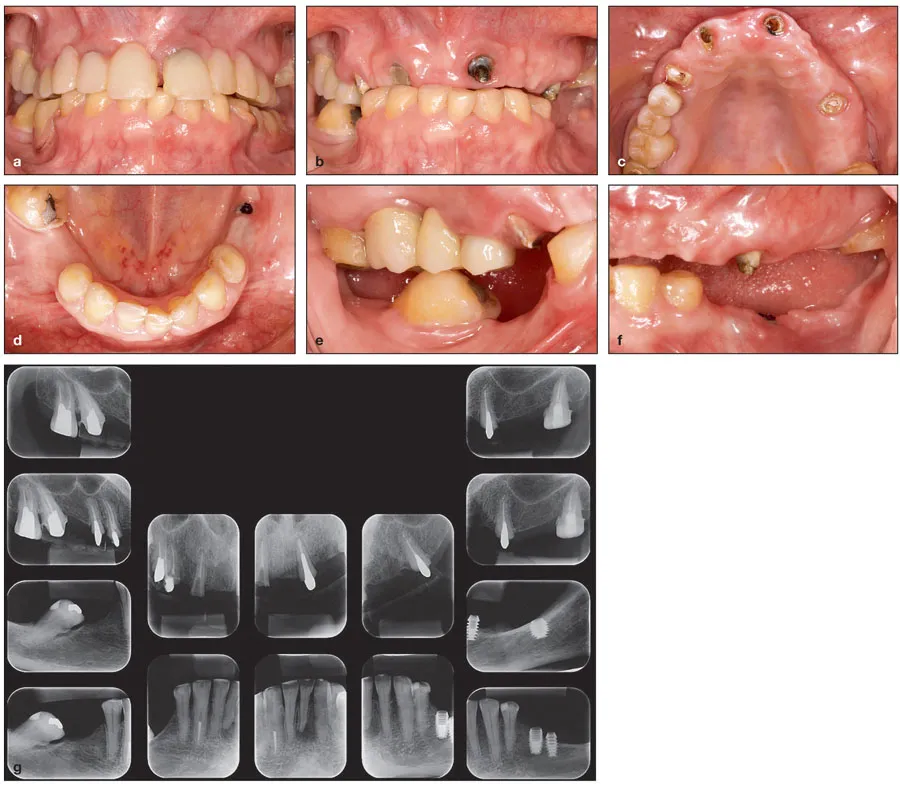

In the initial phase, it is not uncommon for dentists to become puzzled and lose track of what to do to develop a comprehensive and reliable plan of care. The immense number of findings that arise when evaluating a difficult dental case (Fig 1-1) may overwhelm inexperienced practitioners to such an extent that they do not even know where to start or what to do first. Even with experienced dentists, questions such as āNow what am I supposed to do?ā or āHow can I be sure that all the necessary information has been properly assessed?ā are quite common in this phase of treatment. Furthermore, quite frequently there is disagreement as to which specialty or professional should assume the role of organizing and conducting the complete planning process.

Fig 1-1 A complex case involving endodontic problems, tooth position problems, occlusal problems, and temporomandibular joint problems. (a and b) Frontal view of the patient with the existing prostheses in place (a) and removed (b). Note that the occlusal vertical dimension has been altered because of the lack of posterior support. The height of the crowns of the mandibular anterior teeth has been significantly reduced because of abrasion. The maxillary right central incisor has drifted buccally, most likely as a result of the lack of proper support for the forces of mastication. (c and d) Occlusal views of the maxillary and mandibular arches showing the number, position, and distribution of remaining teeth. (e and f) Lateral views of the right and left quadrants showing changes in occlusal vertical dimension. Significant drifting has occurred because of the lack of proper support for the forces of mastication. (g) Periapical radiographs of the maxillary and mandibular teeth. Note the presence of oversized and undersized posts and cores, periapical lesions, and dental implants.